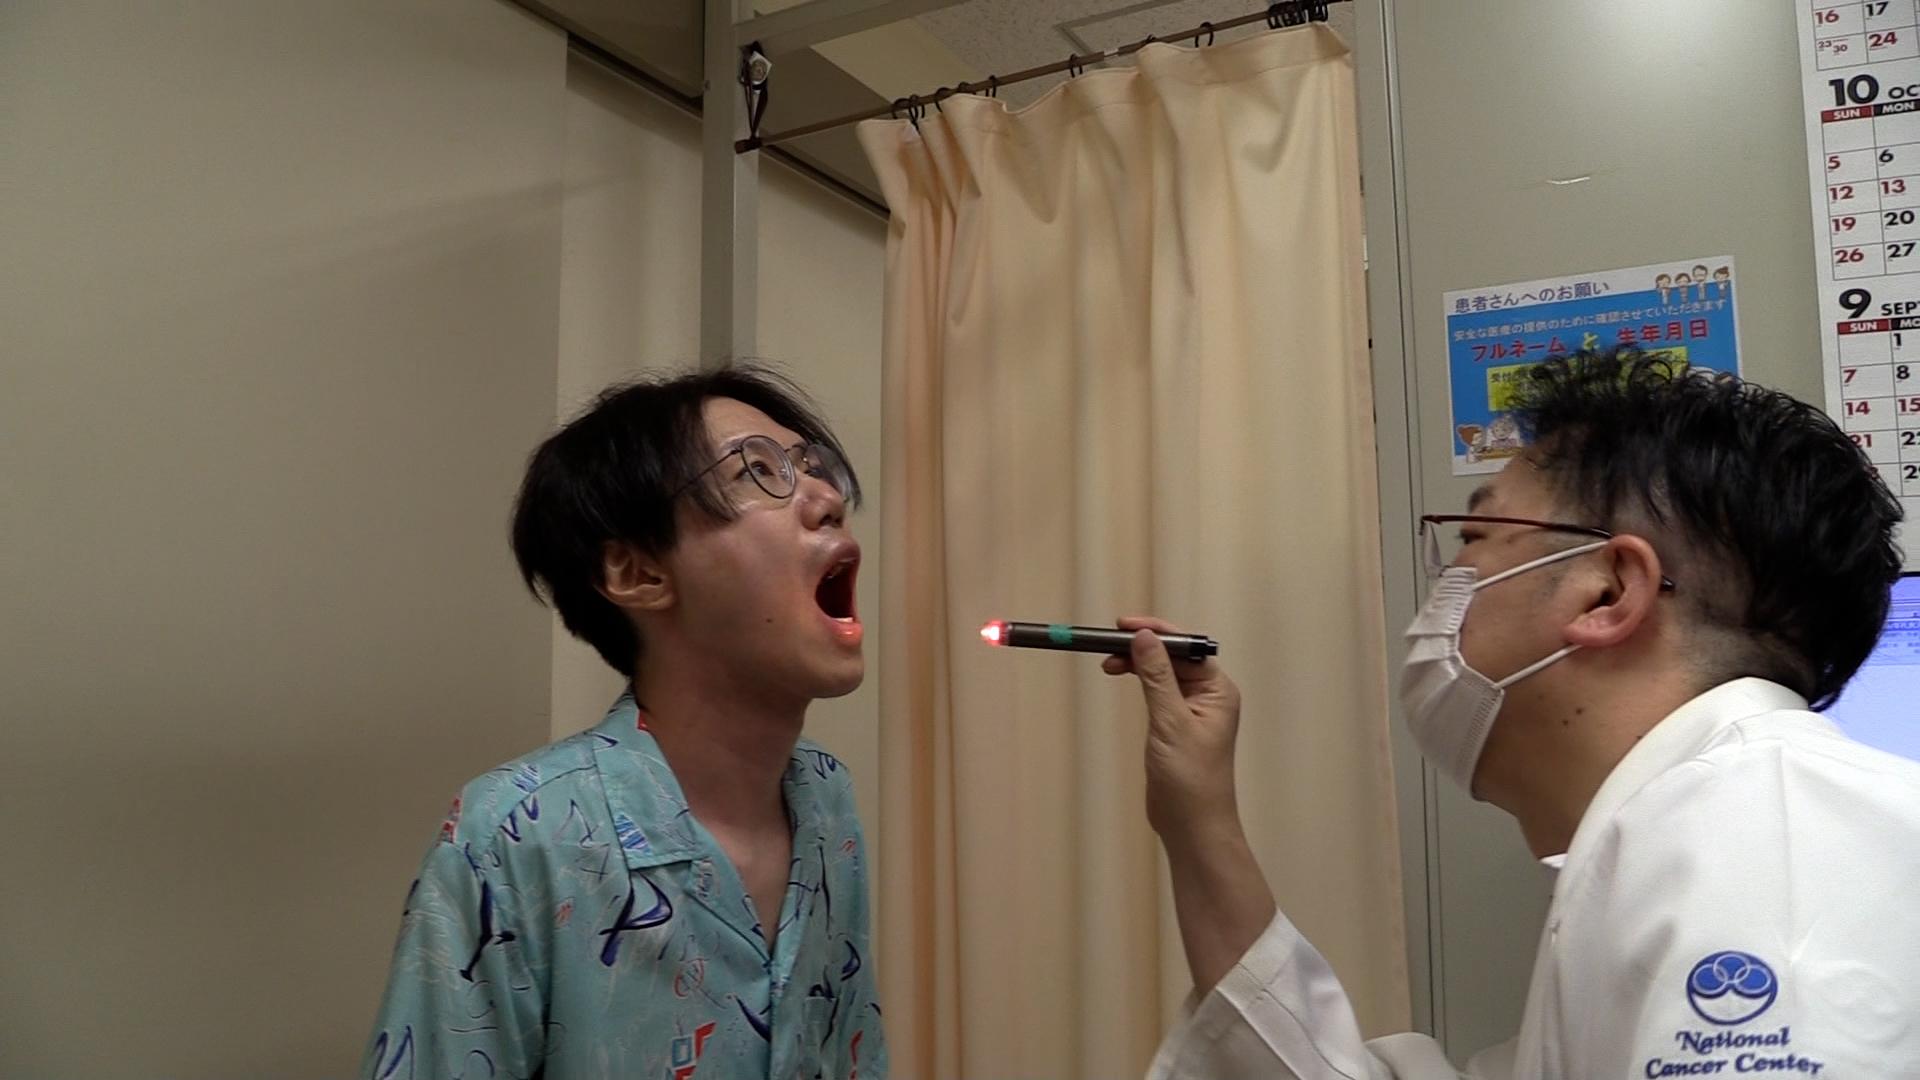

2人に1人が、癌になる時代。外科手術や薬物療法と並ぶ“癌治療の3本柱”の1つが、放射線治療だ。進化する癌の高精度放射線治療の最前線を取材。

2人に1人が、癌になる時代。外科手術や薬物療法と並ぶ“癌治療の3本柱”の1つが、放射線治療だ。「切らずに治せる治療」として身体への負担も少なく、仕事がある“現役世代”の患者が働きながら治療を受けられるメリットがあり、国内で新たに放射線治療を受ける癌患者は年間約23万人に増加している。

その放射線治療は、AIの進化などによる技術革新で、今後さらに治療の精度が上がることが期待されている。しかし、国内メーカーは装置の製造から相次ぎ撤退し、医療現場では海外メーカー製がシェアをほぼ独占する状態になっていた。ガイアは、進化する癌の高精度放射線治療の最前線を取材。これまでにない最新鋭の性能を武器に“悲願の国産装置”を開発した「日立ハイテク」と医師たちの挑戦を追う。